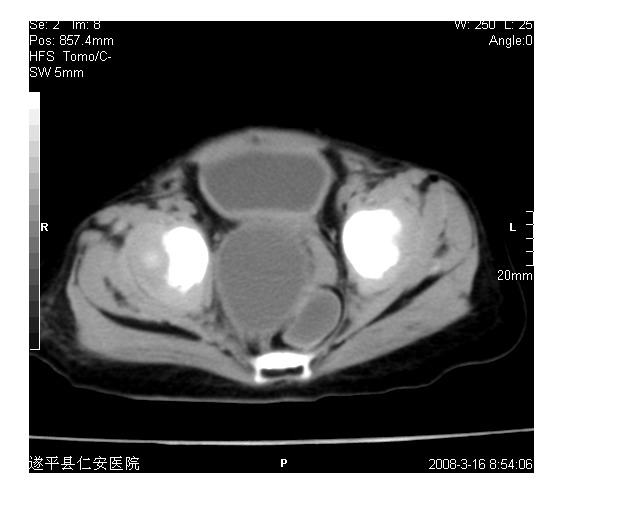

以下是引用lkc8963在2008-3-16 12:49:00的发言:[br]盆底巨大混杂密度肿块,富含多种组织成分包括脂肪/液体/软组织/钙化,边界清楚,向前压迫肠管及膀胱,向后突入骶尾部皮下脂肪层,首先考虑畸胎瘤,诊断时需要与脊柱裂/囊性淋巴管瘤等区别。